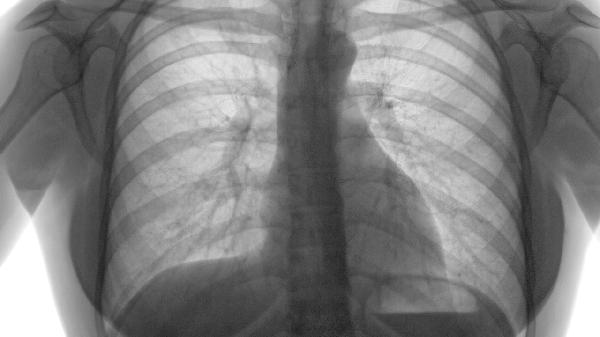

急性加重期合并感染时,炎症因子导致毛细血管通透性增加。需根据痰培养结果选用抗生素阿莫西林克拉维酸、左氧氟沙星、头孢曲松,配合糖皮质激素甲强龙短期冲击治疗。

长期呼吸困难导致进食不足,低蛋白血症引发水肿。建议每日补充1.2-1.5g/kg优质蛋白乳清蛋白粉、鱼肉、鸡蛋,联合维生素B族改善代谢。

肺气肿患者日常需进行缩唇呼吸训练,每周3次有氧运动如八段锦、平地步行,避免接触油烟及冷空气刺激。饮食采用高蛋白、高纤维、低碳水化合物原则,推荐三文鱼西兰花沙拉、百合银耳羹等食谱,睡眠时抬高床头15度减少夜间呼吸困难。定期监测血氧饱和度,当面部水肿持续24小时以上或伴随意识改变时需急诊处理。